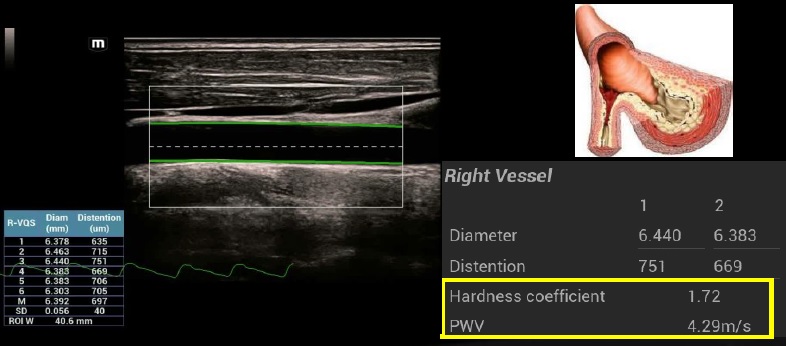

R-VQS

Analýza tuhosti cievnej steny pomáha vo včasnej diagnostike a prevencií cievnych chorôb. Koeficient tuhosti ciev a pulznej vlny (PWV) sú vhodné na včasnú diagnostiku arteriálnej aterosklerózy.